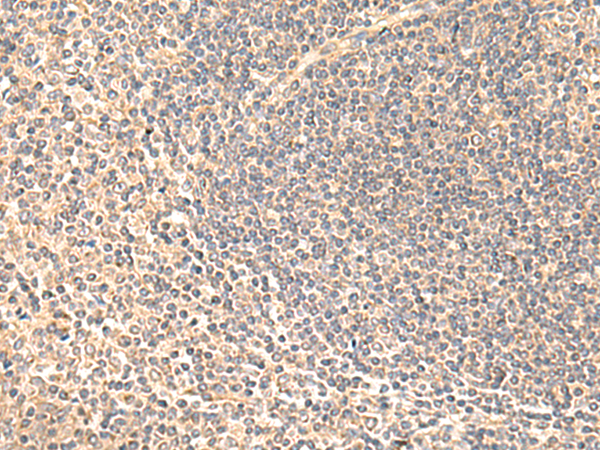

分类: 科研抗体货号: P10061别名: Ntra; KILON; IGLON4; DMML2433应用: WB,IHC反应种属: Human, Mouse, Rat

分类: 科研抗体货号: P10076别名: CRCS1; GalNAc-T12应用: IHC反应种属: Human, Mouse

分类: 科研抗体货号: P10044别名: ARL6; ARF4L应用: IHC反应种属: Human, Mouse

分类: 科研抗体货号: P10075别名: MLS; CCHL; MCOPS7; LSDMCA1应用: WB,IHC反应种属: Human, Mouse

分类: 科研抗体货号: P10060别名: GST; GST13; hGSTK1; GSTK1-1; GST13-13; GST 13-13应用: WB,IHC反应种属: Human

分类: 科研抗体货号: P10043别名: HC7-I应用: WB,IHC反应种属: Human, Mouse, Rat

分类: 科研抗体货号: P10074别名: hMLKL应用: IHC反应种属: Human

分类: 科研抗体货号: P10059别名: Msl1; U2B''应用: WB,IHC反应种属: Human, Mouse

分类: 科研抗体货号: P10040别名:应用: IHC反应种属: Human, Mouse

分类: 科研抗体货号: P10073别名: NST; BRSTL1; SULTX3; BR-STL-1; DJ388M5.3; hBR-STL-1应用: IHC反应种属: Human, Mouse, Rat